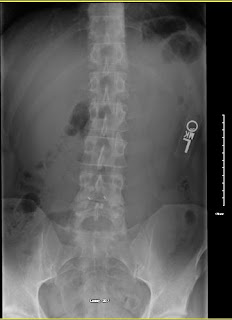

Had my 2 year follow up with MRI and X-ray's last week and I have posted the images below. The surgeon (Dr V) was surprised that the L4 and L5 bones showed signs of improved health ( 2 years ago they both took a beating from the wear and tear on them). The disc is still degenerating but it's seems to have slowed somewhat.

Below are the MRI and X-Ray images:

(X-Ray courtesy of BCH)